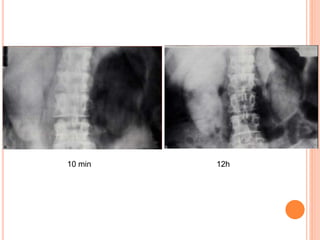

TYPES OF NEPHROGRAM

 Faint persistent nephrogram: hypotension, impaired

function ( High dose urography).

 Increasing dense nephrogram: distal obstruction,

RAS, Renal vein thrombosis.

 Immediate dense: ATN, APN.

 Striated nephrogram: APN, Acute extrarenal

obstruction, ARPKD, Medullary sponge k.

 Patchy nephrogram: Vasculitis.

 Cortical rim nephrogram: Infarction.

10 min 12h